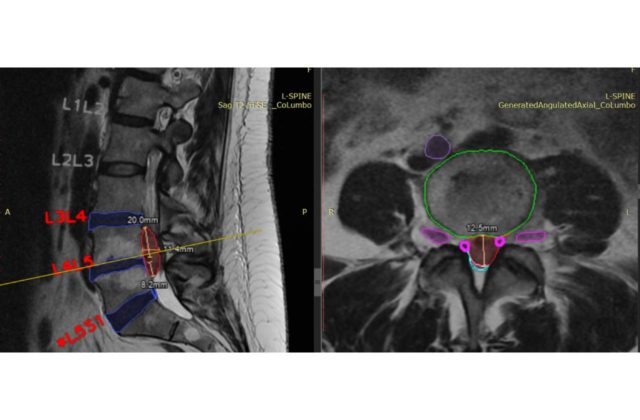

26.4.2023 (SITA.sk) – Unilabs, popredný poskytovateľ diagnostických služieb, nadviazal partnerstvo so spoločnosťou SmartSoft Healthcare s cieľom využiť jej riešenie CoLumbo, ktoré využíva umelú inteligenciu. Chce tak v Španielsku dosiahnuť zlepšenie popisovania a vyhodnocovania vyšetrenia driekovej chrbtice pomocou magnetickej rezonancie.

„Sme nadšení, že môžeme spolupracovať so spoločnosťou SmartSoft a priniesť tak našim pacientom v Španielsku toto inovatívne riešenie. CoLumbo funguje pre rádiológov ako ďalší pár digitálnych očí a pomáha im pri MRI vyšetreniach driekovej chrbtice odhaliť významné patológie. Veríme, že CoLumbo zlepší kvalitu a efektivitu našich MRI vyšetrení driekovej chrbtice a v konečnom dôsledku pomôže našim pacientom i rádiológom,“ povedal prezident Scientific Business Units a medicínsky riaditeľ spoločnosti Unilabs Dr. Christian Rebhan. „Sme nadšení, že budeme prvou krajinou, ktorá toto riešenie vyskúša. Náš technický tím už začlenil tento nástroj do pracovného postupu rádiológov a zabezpečil, že ho možno pohodlne a efektívne využívať,“ dodal generálny riaditeľ Unilabs Španielsko Rainiero Holgado.

CoLumbo skracuje rádiológom čas popisovania a vyhodnocovania nálezom o 25 %, zvyšuje počet vyšetrených pacientov a zároveň zlepšuje presnosť diagnóz. Klinické testy dokázali, že CoLumbo môže znížiť počet chýb z opomenutia až o 15 %.

CoLumbo získal Pečať excelentnosti Európskej komisie. Projekt získal značku CE a je v súlade s reguláciami systémov kvality FDA. Má povolenie FDA 510(K), takže ho možno klinicky používať v Európe i v USA. Čaká sa aj na patent USPTO US 63/239,985.